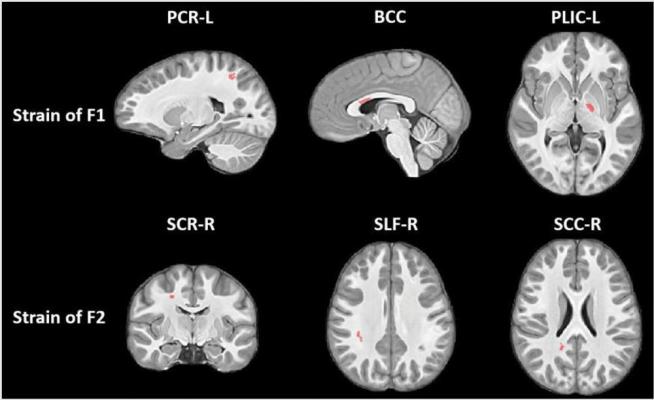

Statistically significant clusters (red-colored) showing group differences (Control vs. Football) in white matter strain along the primary (F1) and secondary (F2) fibers. While body of corpus callosum (BBC) showed relative shrinkage in Football group, the other clusters showed relative stretching of fibers. PCR: Posterior Corona Radiata, PLIC: Posterior Limb of Internal Capsule, SCR: Superior Corona Radiata, SLF: Superior Longitudinal Fasciculus, SCC: Splenium of Corpus Callosum. Image courtesy of Kim et al.

Kim and colleagues studied the results of these collisions on youth football players using a novel MRI method that looks at the strain evident on white matter tracts — the bundles of nerve fibers that carry information between different areas of the brain.

"The focus here was on deformations of these fiber bundles," Kim said. "Changes from collisions might cause elongation or contraction of these bundles."

The MRI results showed the football players developed changes in the corpus callosum, a critically important band of nerve fibers that connects the two halves of the brain. The primary role of the corpus callosum is to integrate cognitive, motor and sensory functions between the two sides of the brain.

There were signs of greater axial strain (contraction) in some parts of the corpus callosum, and indications of radial strain (expansion) in other parts.